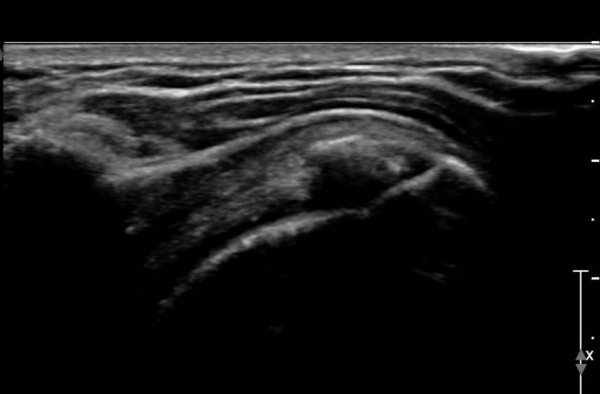

°ß°©ÇÏ±Ù°Ç Á¾´Ü¸é°Ë»ç(»çÁø 2)¿Í ȸ´Ü¸é°Ë»ç(»çÁø 2)¿¡¼­ ÈĹæÀ½¿µÀ» º¸ÀÌ´Â °í¿¡ÄÚ ¼®È¸°¡

°üÂûµÈ´Ù. Åë»óÀûÀÎ °ß°©ÇÏ±Ù°Ç Á¾´Ü¸é°Ë»ç¿¡¼­´Â °ß°©ÇÏ±Ù°Ç »óºÎ ¼®È¸È­·Î º¸ÀÌÁö¸¸ Ⱦ´Ü¸é°Ë»ç·Î

º¼ ¶§ °ß°©ÇÏ±Ù°Ç ÇϺο¡ ¹ß»ýÇÑ ¼®È¸ÀÓÀ» ¾Ë ¼ö ÀÖ´Ù.